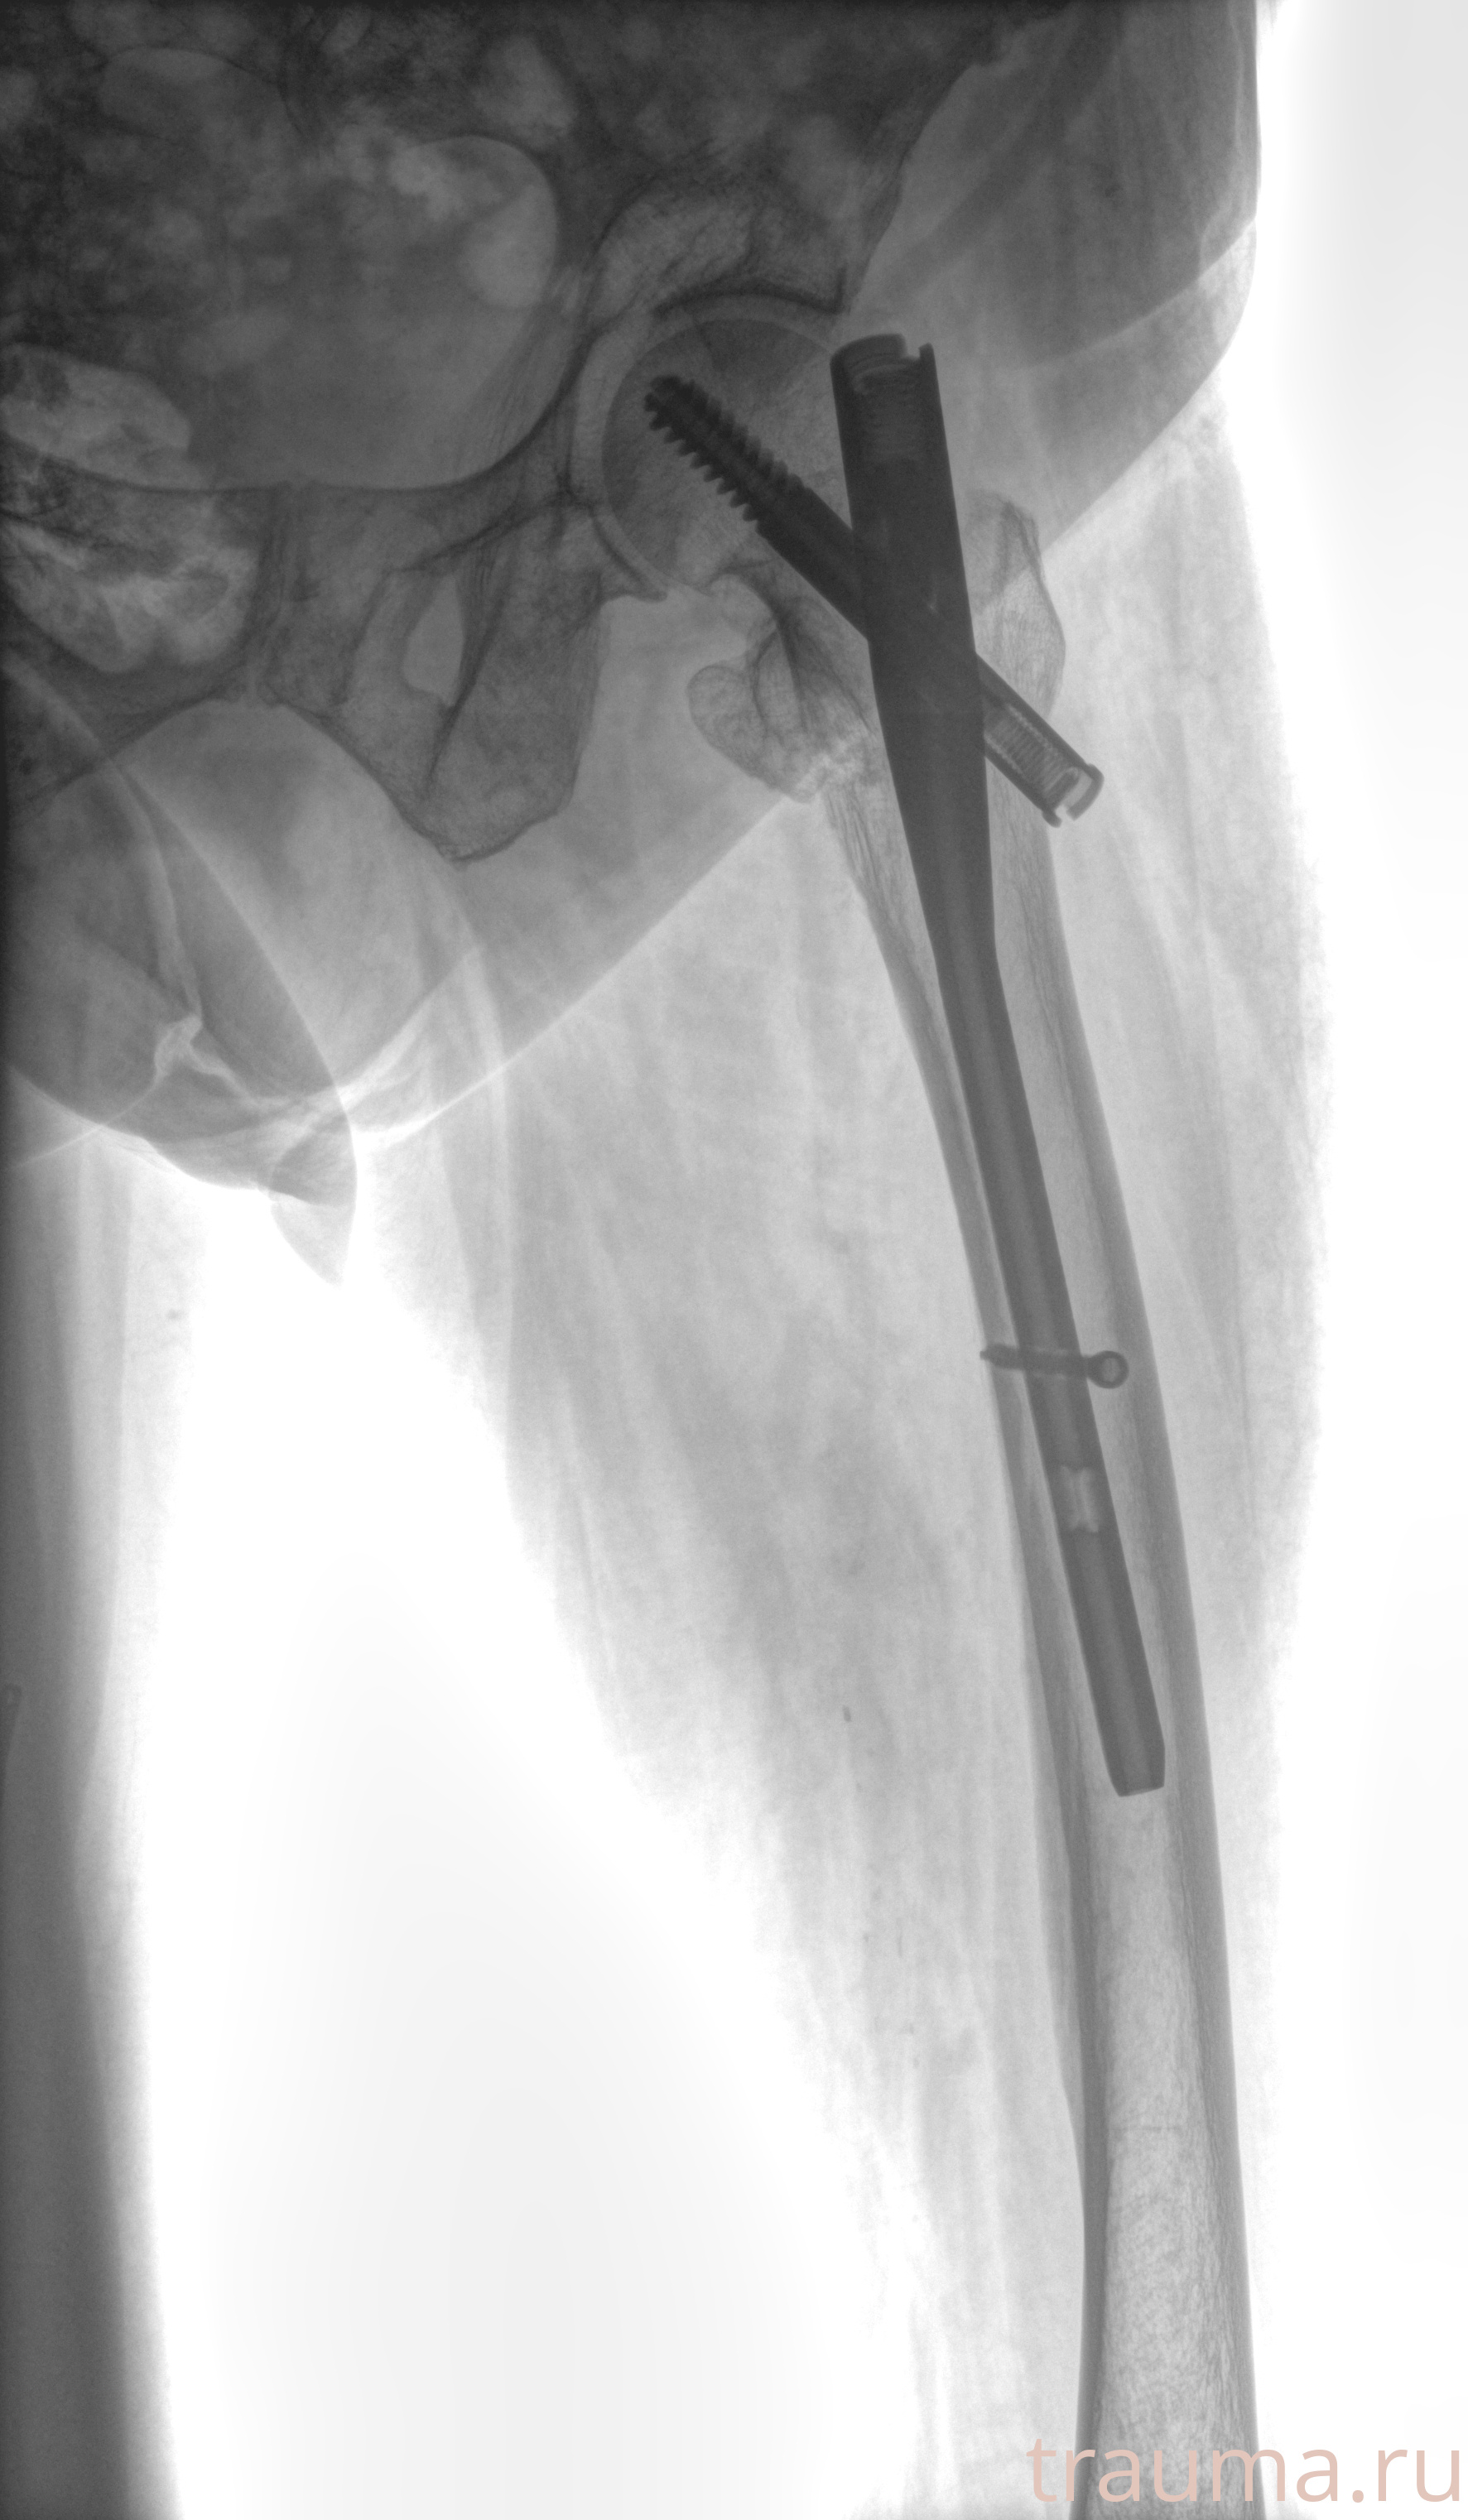

Рентгенограммы

Рентген на дому: по вашему адресу приезжает врач-рентгенолог, травматолог-ортопед с мобильным рентгеновским аппаратом, проводит диагностику травмы или заболевания, делает необходимые рентгенограммы, дает рекомендации по дальнейшему лечению. Получить качественные снимки в домашних условиях возможно благодаря уникальной методике, разработанной МосРентген Центром для института  Склифосовского